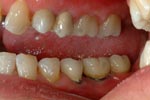

Caso finito